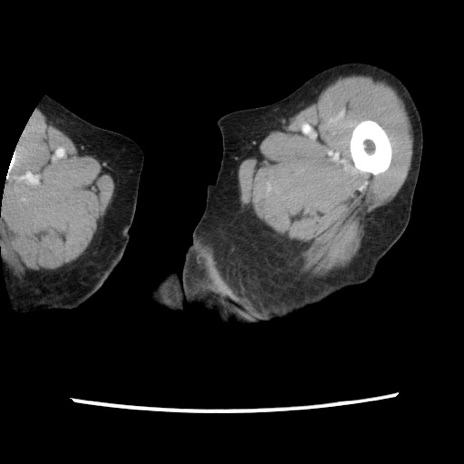

冠状断像